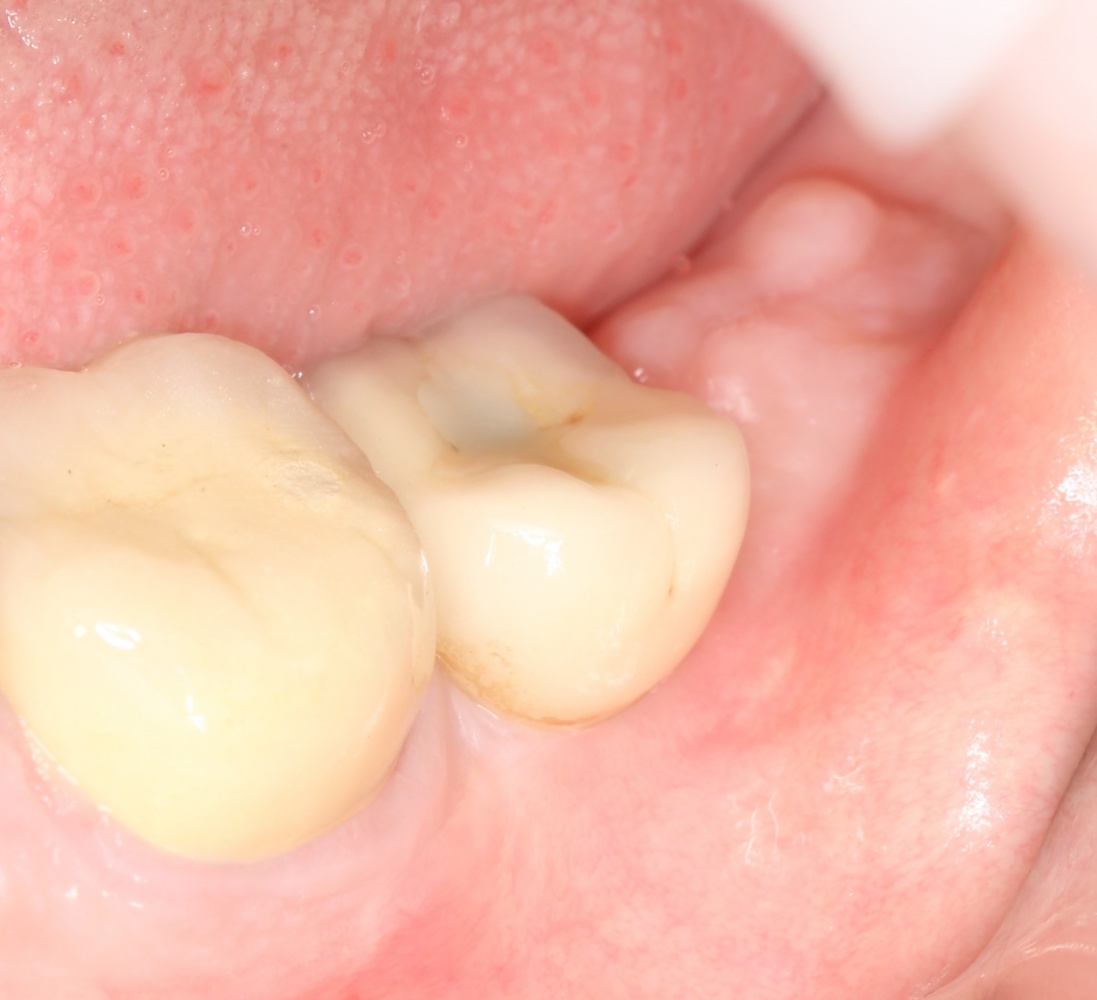

Рекомендации по установке имплантов. Для всех. Часть V.